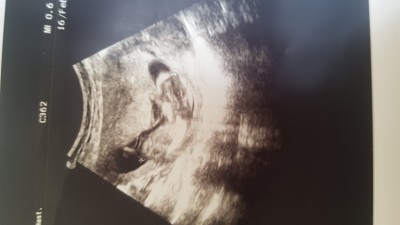

13 haftalık hamileyim cinsiyetini anlayan var mı:)

Gebelik haftası 13

Burdan nasıl anlaşılsın çocuk yan yatıyor burda. Doktor bacak arasına girip görüyor resmen.

Muhtemelen kız canım. Benim oğlum 13 haftalıkken her yeri belliydi. Kızlar genelde et parçası gibi oluyorlar. Sonradan şekilleniyorlar. Allah sıhhatle kucağına almayı nasipp etsin inşallah

Bu erkek:) kesin